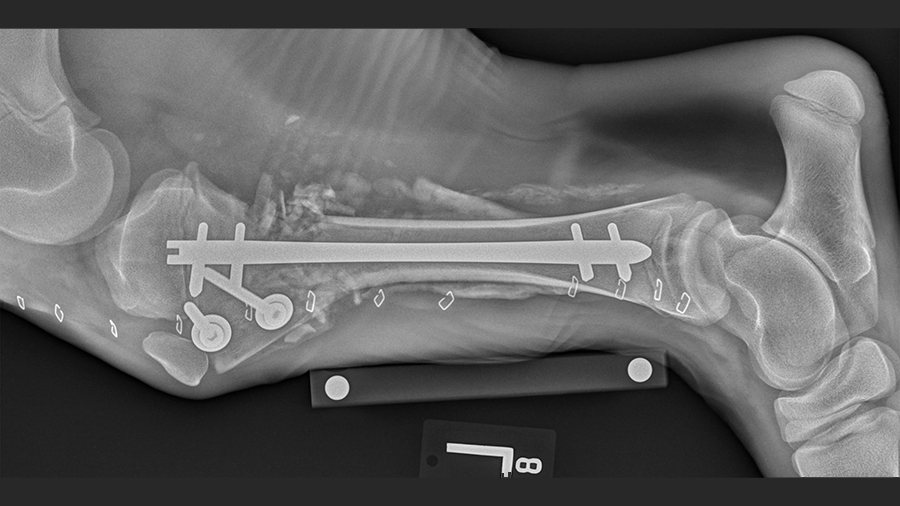

The interlocking nail: an impressively small solution with a lot of strength

Déjardin explains: “During surgery, reduction was difficult, because I could not manipulate the bone fragments with any surgical tools without risking creating secondary fractures. I had to do a small, two-centimeter resection to realign the cranial metaphyseal fragment. The impetus for using a nail rather than a plate was threefold: 1) being inside of the bone, the nail cannot fail by pulling out of the bone as a plate might do in soft bone, 2) the nail could go through the growth plate with significant risk of affecting bone growth, and 3) both locking bolts could be anchored below the growth plate. I put an 8mm x 160mm I-Loc interlocking nail with two bolts proximally and distally into the bone. Because the bone was so soft, I was able to lightly press the nail in.”

“Interlocking nails range from 3 to 8 mm in diameter, and we used the largest size available on Lulu, who was 100 pounds at the time of fixation,” says Déjardin. “Lulu offered us the unique opportunity to study the nail, as at surgery, she was the weight of a large breed dog, yet had the potential to become much taller and heavier very quickly. Indeed, Lulu was approximately 450 pounds just six months after surgery and is 700 pounds today.”

Radiographic evidence showed that the surgery was a complete success, Déjardin says.

“Lulu was discharged two weeks later. Successive CT scans and radiographs showed that the nail was well-centered, allowing for symmetrical growth, and that the nail’s small footprint did not impact the physis and normal axial growth,” Déjardin explains.